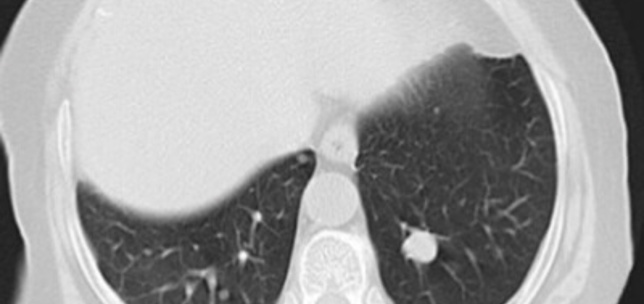

Urologic Oncology